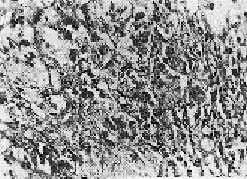

The diagnosis in each case was confirmed by the histopathological study of biopsy material from the liver. Liver biopsies were performed with a Wilms Silverman needle. The material was fixed, stained by standard staining methods and examined microscopically, (Figs. 4 and 5) to evaluate the cirrhotic stage. Such biopsies revealed cirrhotic degenerative changes (Grade II). Intracytoplasmic globule infiltration could be seen in the specimens studied.

Fig. 4 : Biopsy of an I.C.C. liver specimen showing degeneration and infiltration. (Grade II changes).

H & E, 40 x 7